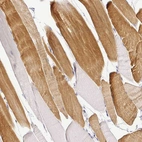

Immunohistochemistry analysis in human skeletal muscle and liver tissues using HPA053903 antibody. Corresponding HMCN2 RNA-seq data are presented for the same tissues.